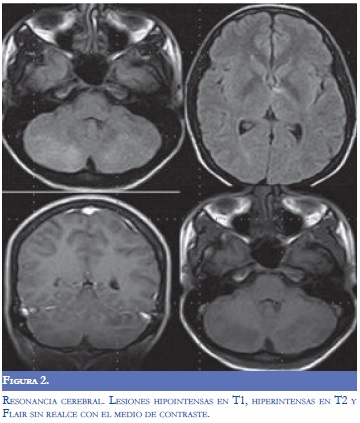

Por el deterioro progresivo y el compromiso predominantemente de la fosa posterior, se consideraron como diagnósticos diferenciales trombosis venosa cerebral profunda o encefalitis de tallo. La resonancia magnética cerebral practicada seis horas después del deterioro neurológico, (Figura 2) evidenció lesiones hiperintensas en T2 e hipointensas en T1 en ambos lóbulos cerebelosos, tallo cerebral, corteza calcarina y región talámica izquierda. Algunas de estas lesiones realzaron con el medio de contraste, pero no hubo realce meníngeo. La angiorresonancia y la venografía por resonancia no mostraron alteraciones.

Los hallazgos paraclínicos incluyen leucocitosis, elevación de la VSG y PCR, y pleocitosis e hiperproteinorraquia en el líquido cefalorraquídeo (9,11,12). Con respecto a las imágenes diagnósticas, la tomografía de cráneo puede ser normal o demostrar alteraciones inespecíficas (5). La resonancia magnética cerebral demuestra hiperintensidades multifocales bilaterales irregulares en las secuencias con información T2 y FLAIR, hallazgos sugestivos de edema cerebral extenso y áreas de hemorragias puntiformes demostradas en las imágenes de susceptibilidad magnética. Estos últimos hallazgos son útiles en el diagnóstico diferencial dado que no suelen encontrarse en ADEM (13). El compromiso se localiza característicamente en la cápsula interna, el tallo cerebral, el cuerpo calloso, el lóbulo parietal y el cerebelo (6,11).